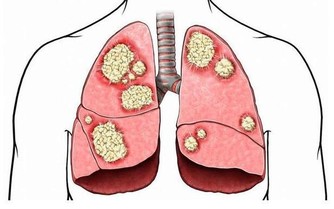

氣從鼻入搓鼻潤肺,提高免疫力

常搓鼻翼,能改善鼻子的血液流動情況,提高鼻子的功能。對於各種鼻炎也有很好的防治作用。

鼻子功能正常,則會減少更多空氣中的有害物質進入身體,

使得吸入肺內的空氣更加清潔、濕潤、溫暖,提高我們抵抗疾病的能力。

方法:用食指和中指沿鼻翼兩側上下搓,搓100次。遇到酸痛的地方,可適當點按。